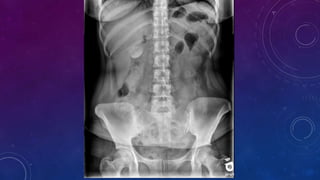

• Multiple pelvic phleboliths.

• Small well-defined round osseous lesions in the left

side of the abdomen, adjacent to midline represent

calcified lymph node in the para-aortic and left

common iliac groups, also visualized on the

corresponding CT.